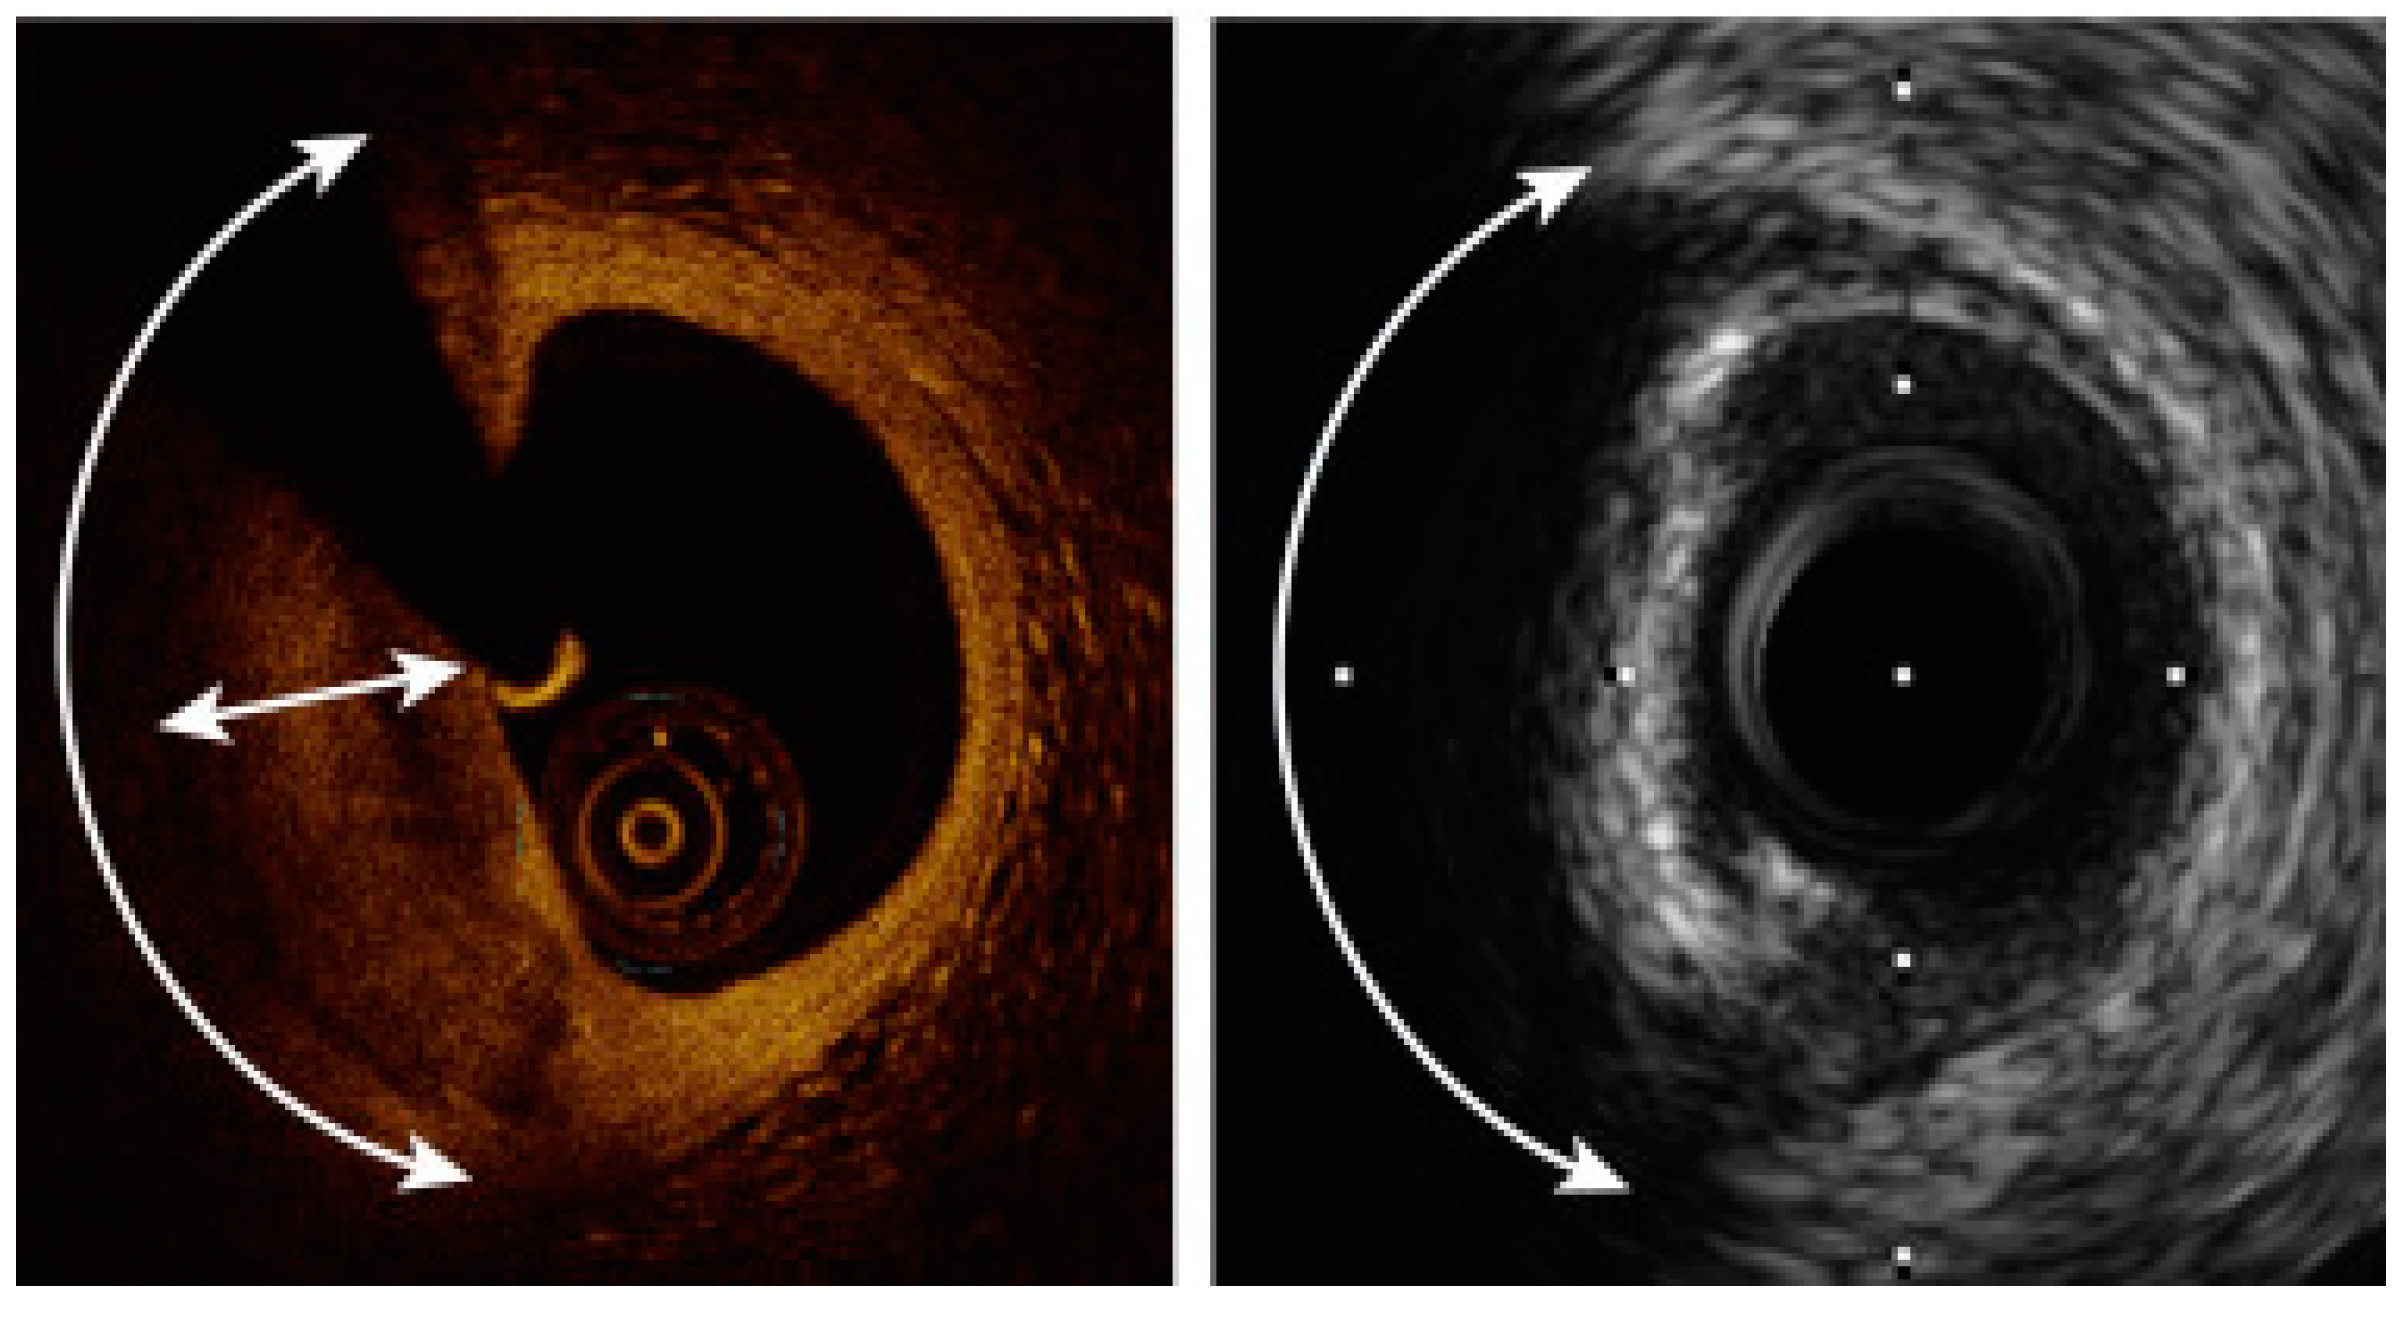

Figure 3.

OCT vs. IVUS measurement outcomes.

Moreover, OCT can detect plaques prone to rupture. The advantage of OCT stems from its higher resolution in comparison to IVUS, which allows a more precise assessment [] (Figure 4). Rui et al. analyzed 348 slices from the same lesions using both OCT and IVUS. The mean value difference between OCT and IVUS cap thickness measurements was 1.83% (p = 0.031). However, the mean value of point-to-point differences was 35.76%. The study group concluded that there were significant differences between IVUS and OCT plaque cap thickness measurements []. Similar conclusions were made by Ueki et al., who analyzed lesions with RF-IVUS and OCT. Out of the 208 lesions classified as TCFA (thin cap fibroatheroma) by RF-IVUS, 14 (6.7%) were also classified as TCFA in OCT, 60 (28.8%) as ThCFA (thick cap fibroatheroma), 101 (48.6%) as fibrosclerotic, 29 (13.9%) as fibrous and 4 (1.9%) as a normal vessel. All OCT assed TCFA (n = 14) were confirmed as TCFA by RF-IVUS. The concordance rate between RF-IVUS and OCT for TCFA diagnosis was 29.7% [].

Figure 4.

An example of a comparison between OCT- and IVUS-derived images and measurements of the same lesion in the circumflex coronary artery. The minimal lumen area was 2.75 mm2 in OCT and 3.50 mm2 by IVUS. Adapted with permission from []. Under an Elsevier User license, copyright year 2013.

A comparison between the same calcified plaque. To the left an OCT image, to the right an IVUS image. The calcium angle (curved arrow) can be measured by both modalities and is 130°; however, calcium thickness (double-headed straight arrow) can only be measured by OCT. Adapted with permission from []. Under Elsevier User license, copyright year 2017.